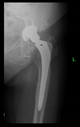

The radiological examination allowed us to verify the close bone-to-implant contact and the unchanged position of the implant during follow-up.

In all the cases operated with the above-described targeting procedure, the stems of the cups remained between the cortical bone surfaces without perforation of the linea terminalis, as shown by postoperative radiographs. There were no complicated surgical situations. In 16 cases, the wound healings were uneventful, and the hips were able to bear weight again after postoperative rehabilitation.